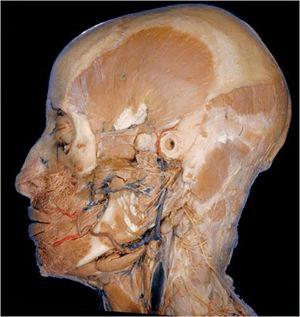

4.对大脑左侧进行的深层解剖,展现出面部的大量血管(红色的代表动脉,蓝色的代表静脉)和神经(灰白色)。脑袋上的孔是外耳道。在左侧头骨上,用于咀嚼的颞肌是像扇子形状的突出的肌肉,它位于嘴巴的后面和下巴的上面。